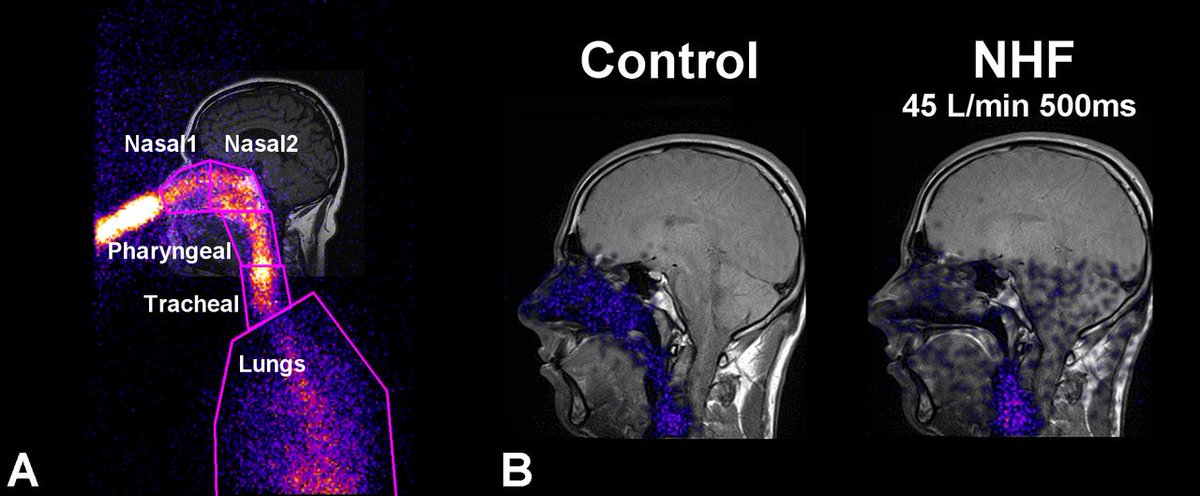

Nasal high flow reduces dead space - new

#openaccess article in@japplphysiol http://jap.physiology.org/content/122/1/191 …pic.twitter.com/f2g3u9SVnR